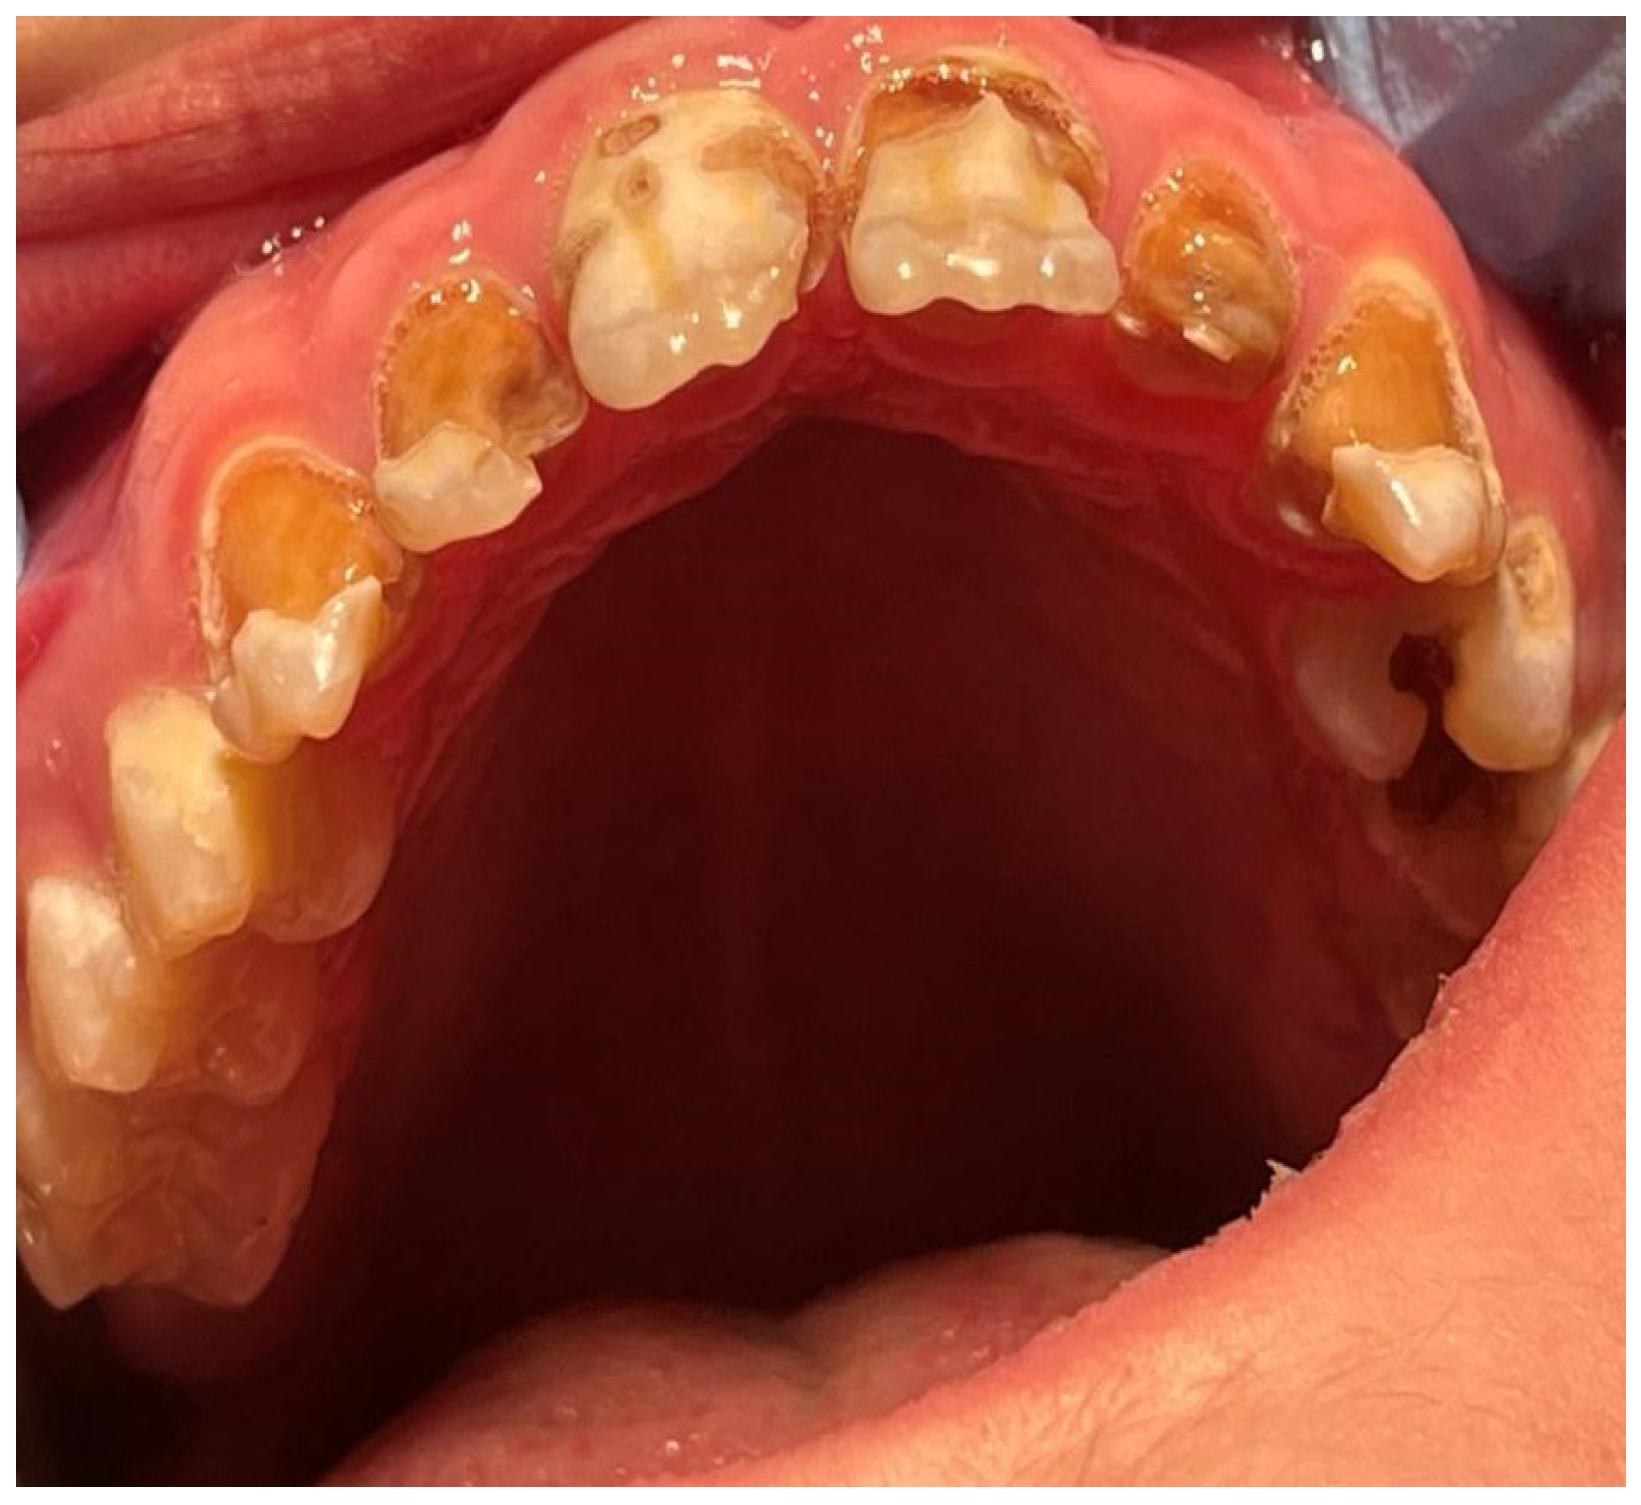

2. Case Report